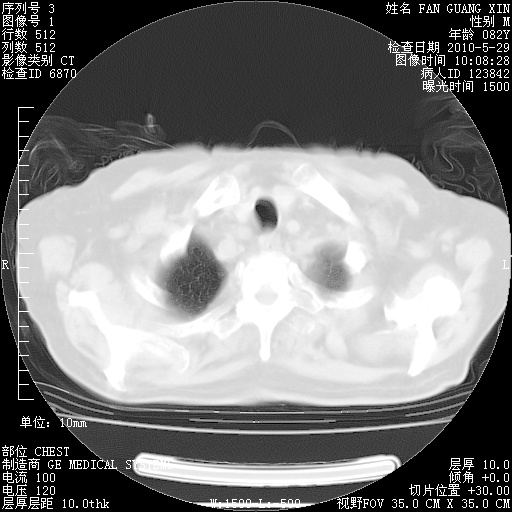

再治疗10天后的肺部CT

再治疗10天后的肺部CT 纵膈窗

肺部体征:呼吸25次/分,心率100次/分,呼吸音增粗。无干湿罗音。

血常规:15.36×10 [sup]9[/sup]/L  N0.92  L0.036  M0.045 ESR 27mm/h。

血生化:白蛋白33.30g/L  球蛋白23.67g/L  CRP 32.82mg/L 肝肾功能正常。电解质正常。

从白细胞总数和中性比例看好像合并感染。肺部纹理好像比上次多,支气管炎?其他感染?

阅读此次胸部CT,肺间质渗出性改变较入院时有吸收。目前从体温、白细胞、中性分叶明显增高,肯定存在细菌感染(发生医院感染哦,若无消化道及泌尿系统等感染的依据,肺部感染可能大)。若你院头孢哌酮舒巴坦钠耐药率较高,同意你的方案,若48小时体温仍高,可考虑使用碳青霉稀类抗菌药物,同时可予超声雾化、注意滴数时加大液体量。白蛋白33.30g/L较低哦,需加强营养等支持治疗。